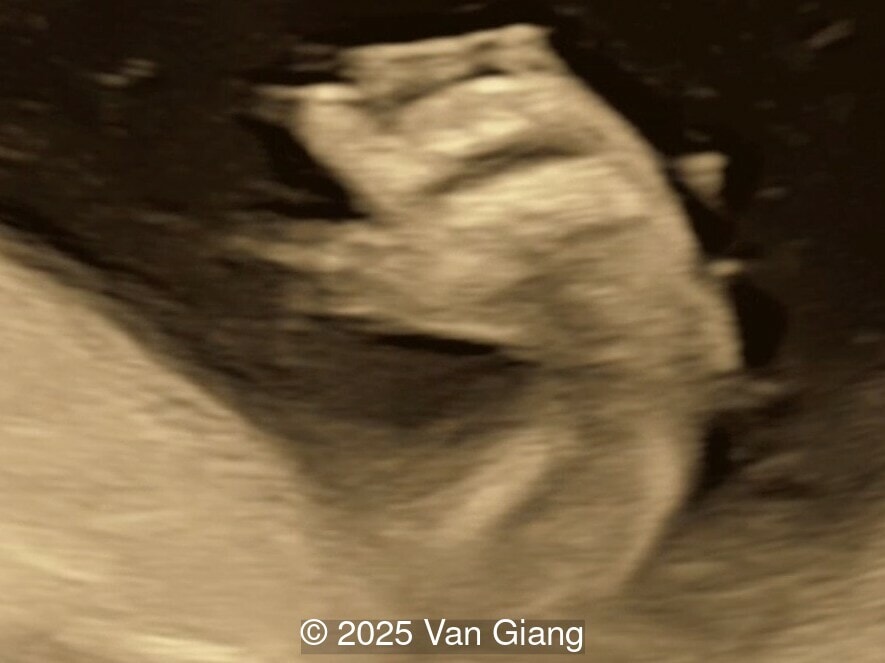

A 32-year-old primigravida presents at 20 weeks gestation without first trimester screening. Ultrasound reveals a small for gestational age fetus with the following anomalies:

fetal face

Image 2 fetal face

Ultrasound revealed severe mandibular and zygomatic hypoplasia, glossoptosis, cleft palate, and micrognathia with an abnormal facial profile. Both upper limbs showed radial ray sequence with abnormal thumbs and shortened forearms. Unilateral clubfoot was also noted. No major cardiac or visceral anomalies were observed. Based on these findings, Nager syndrome was suspected.